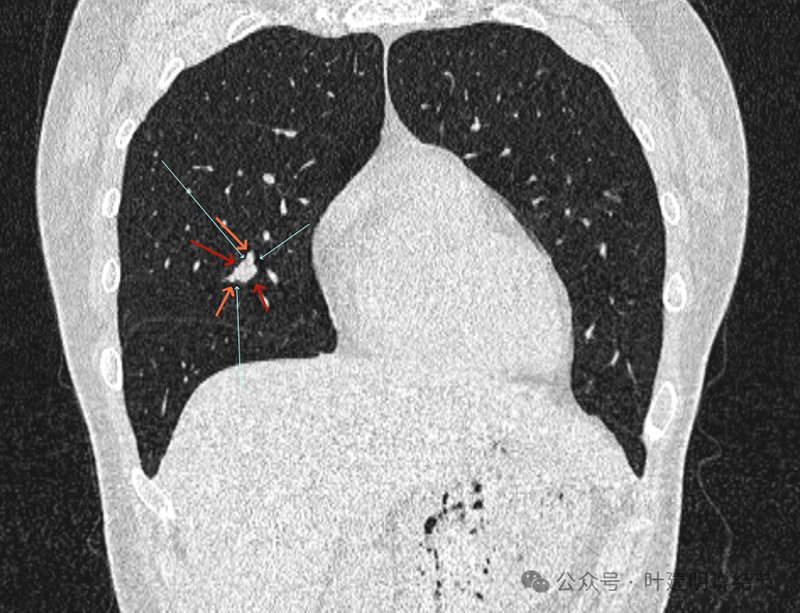

再看冠状位影像:

血管与病灶的关系,两者密度稍不同,天蓝色细箭头所指是分界线。

血管征明显。

血管围着病灶,病灶有膨胀性,表面欠平滑。

不而有膨胀性,血管贴着并被压迫。

边缘欠平滑,邻近血管间隙欠清晰。

血管贴着,结节膨胀。

也示血管与病灶的关系。

结节实性。